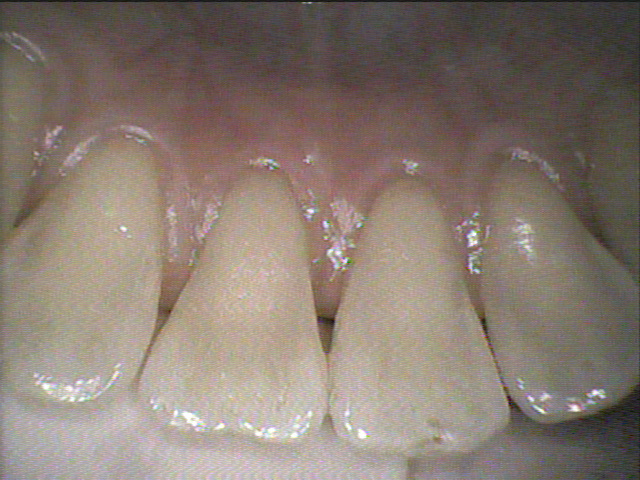

◎クリーニング後

歯と歯の間や、歯と歯茎の境目の歯石を除去し綺麗になりました!✨

これからもクリーニングを続けていきましょう。😊